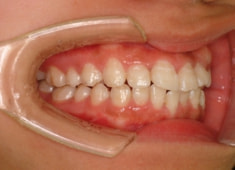

治療開始時